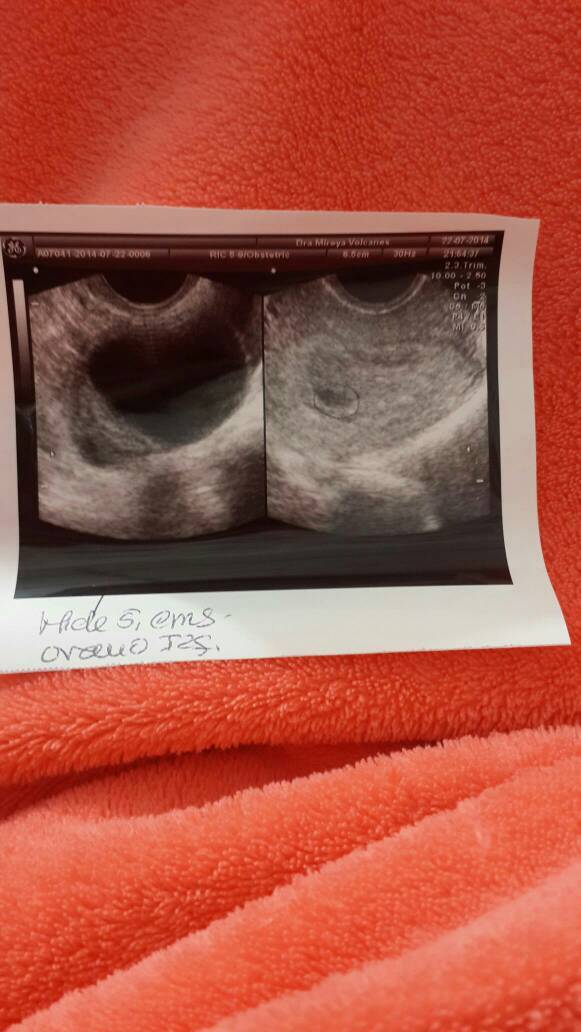

医生帮我看看这个有问题吗? 医生帮我看看这个有问题吗? 点击展开 贝比贝比 2014-07-24 11:27 为您推荐: 其他回答 你好,只是提供图片看不出什么,建议提供数据,一般检查后及时给产检医生看即可,如果有异常的也会告知 专属于你8 2014-07-25 09:02 我不是医院。 许韩哲妈妈 2014-07-24 11:28 相关问题 医生帮我看看,这个有问题吗宝宝? 医生帮我看看,宝宝健康吗?宝宝个大不大 医生们好,请帮我看看这有什么问题吗?6月24号的,现在我需要去检查吗